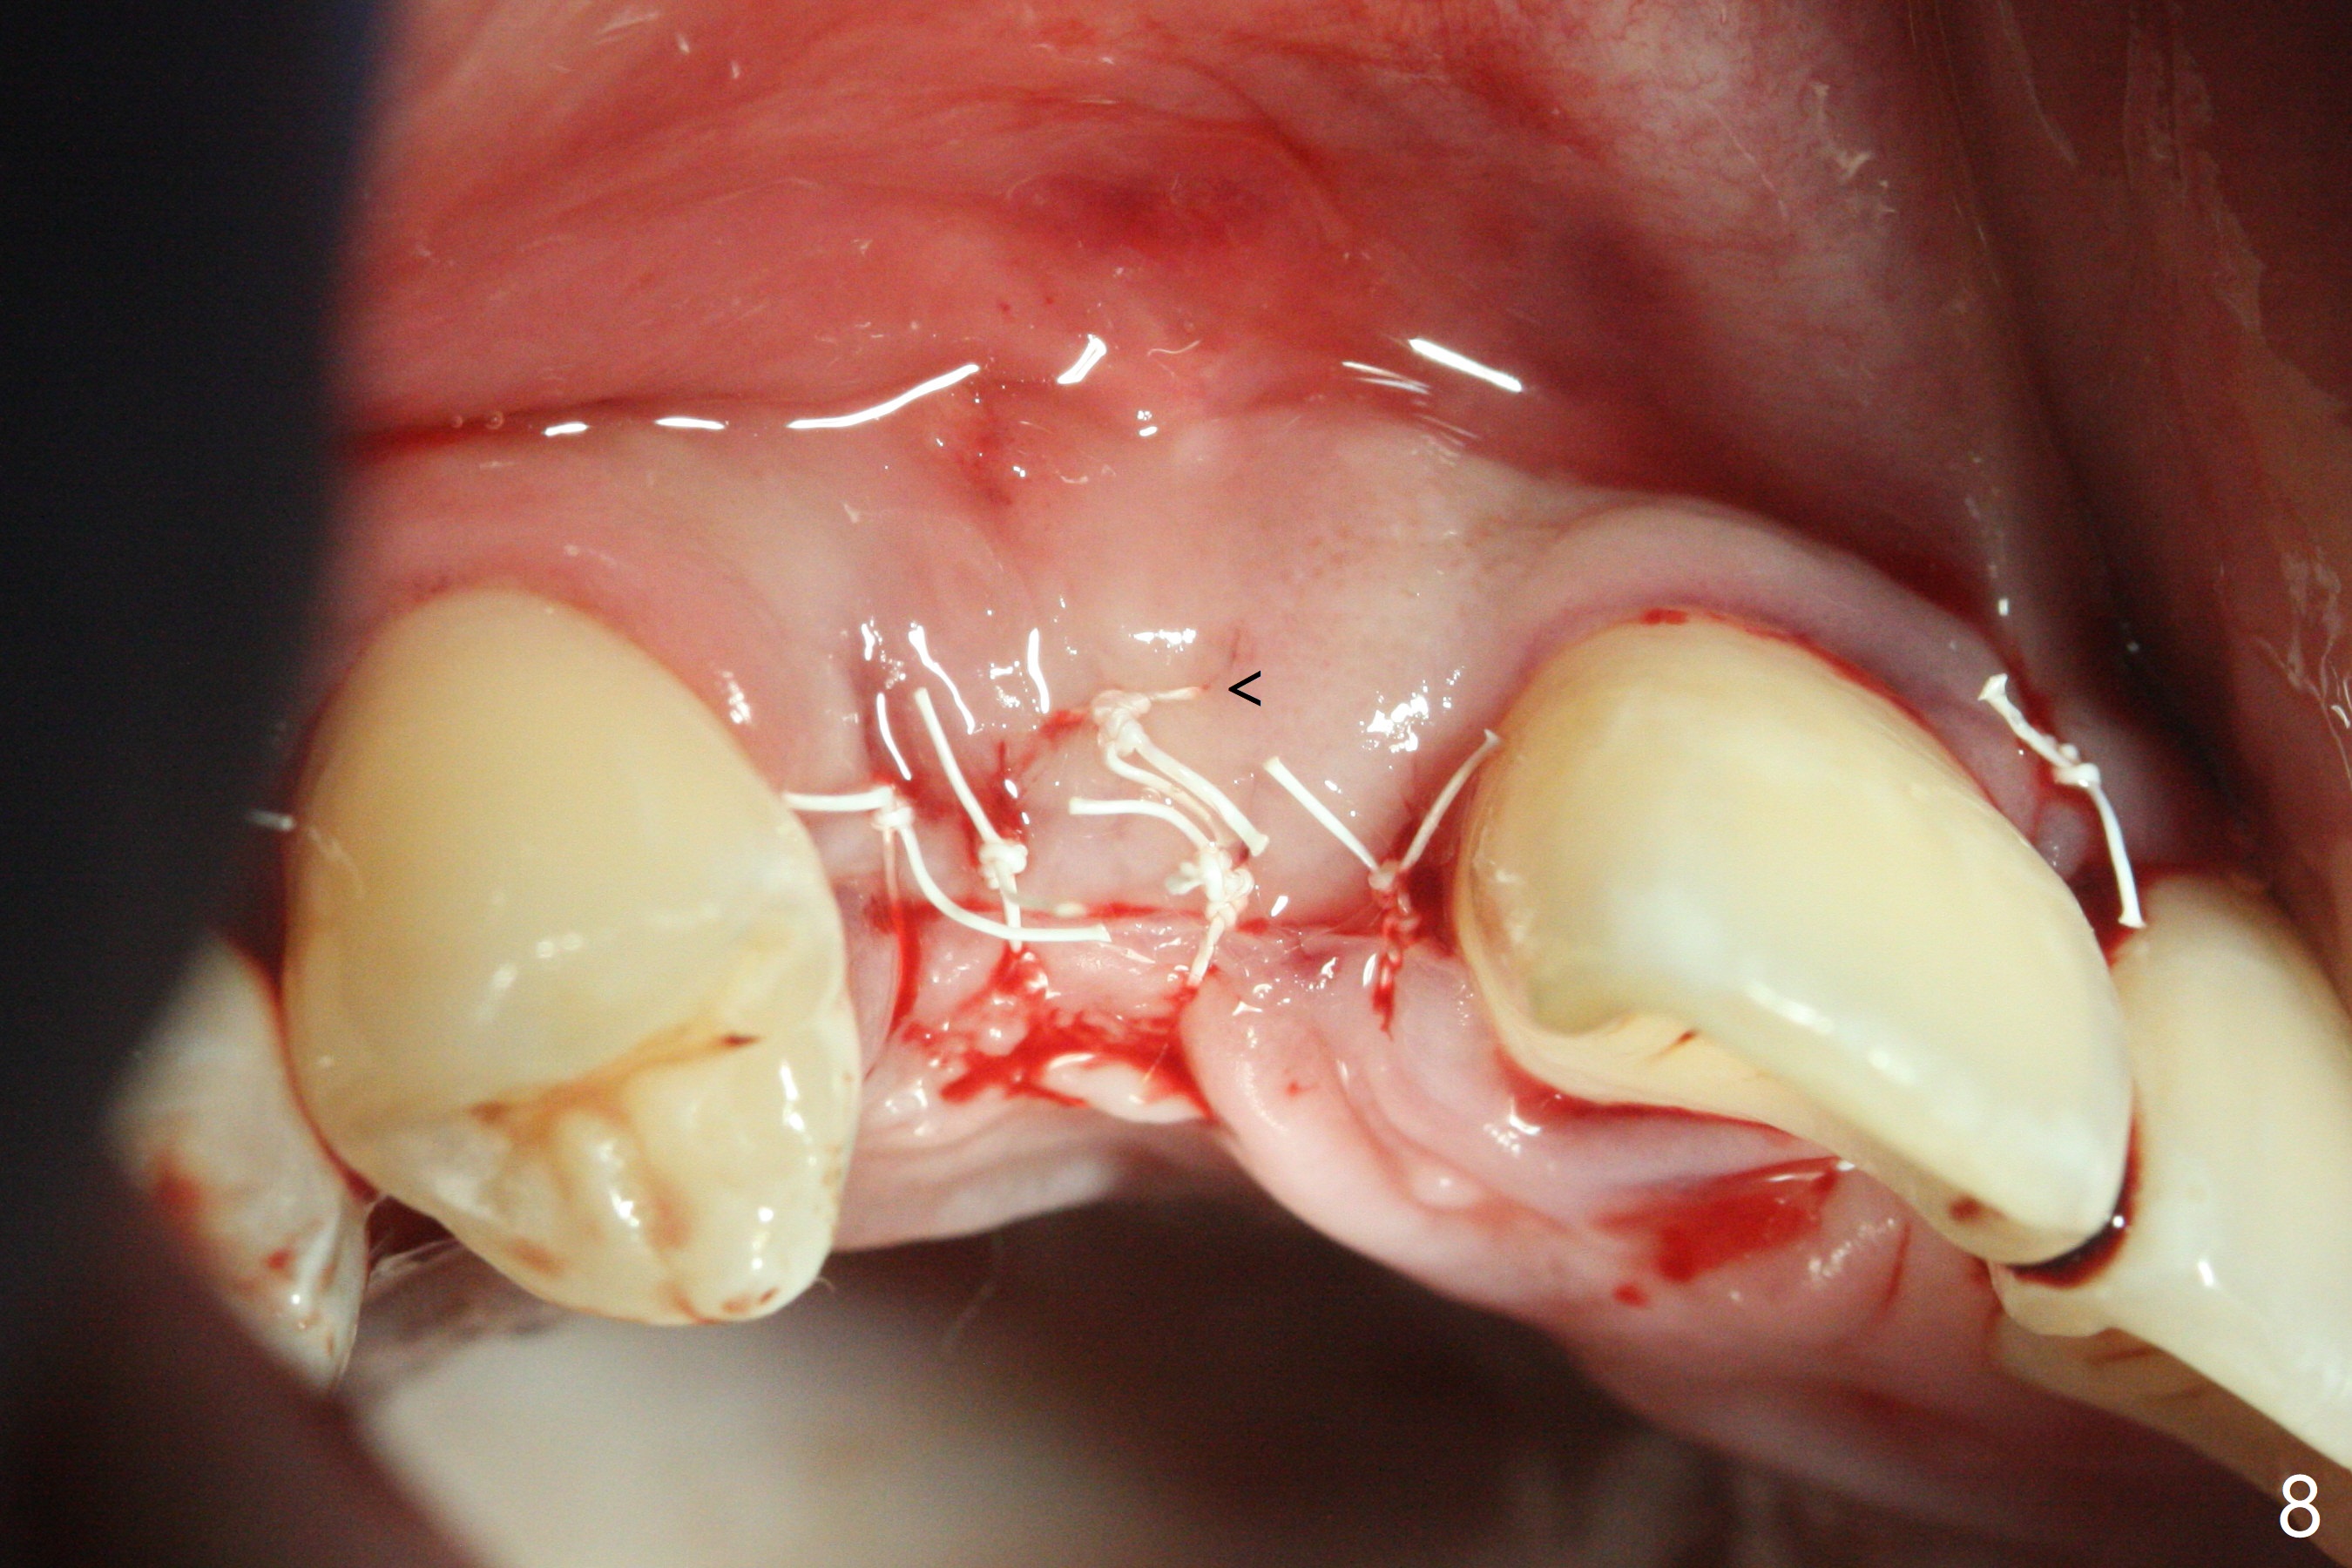

18岁男从外州大学回来,无症状,但是6号牙(右上尖牙)颊侧瘘道(图一,二(角化龈充分(箭头))),根尖片显示植体近中骨吸收(图三:*),而对侧植体仿佛骨整合(图四)。患侧切开后发现植体颊侧暴露,松动。拔除后骨缺损由粘性骨粉修复(图七,九:*),覆盖PRF膜(图七:P)和带钛网(图九:^)不可吸收膜(图五-七),后者用两个小钉子固定(图六(腭侧),七(颊侧),九),使用新的刀片和一个特殊尖头剥离器在颊侧骨膜下相当广泛分离,使用PTFE缝线,粘膜下水平褥式缝合之后(图八:箭头),多个垂直间断缝合,两个乳头垂直褥式缝合。术后一周伤口没有裂开,术后疼痛肿胀已经消退(图十)。术后十八天牙槽嵴仿佛比对侧还要宽(图十一,三与图十二,四(取模)对比)。术后5.5个月伤口没有裂开,牙槽骨,角化龈宽(图十六),与钛网和两个小钉子固定有关(图十五,十七)。CT显示牙槽骨只能容纳2.5或者3.0毫米植体(图十八)。11号牙植体牙冠粘固后没有骨质吸收(图十九),其实10,11号牙颊侧骨板隆起(图二十至二十二),而6植体失败,颊侧骨板吸收,甚至累及5号牙(图十七)。